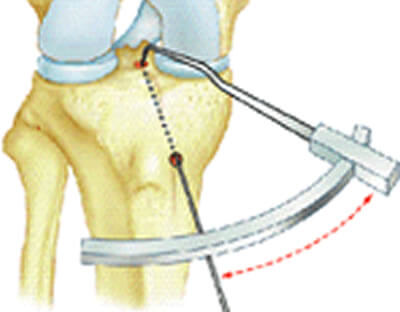

Principe de l'utilisation du viseur

La pointe est introduite dans l'articulation et posée sur le repère choisi.

Une broche est introduite dans le canon du viseur. Elle traverse l'os et sa position est vérifiée et éventuellement modifiée si besoin.

Positionnement du viseur

La broche est posée et sa position vérifiée en allongeant la jambe

La position de la broche une fois vérifiée (et éventuellement modifiée), une première mèche est glissée sur la broche pour créer le tunnel; nouvelle vérification, puis passage de la mèche du diamètre de la greffe.

La zone d'insertion est repérée et nettoyée; le viseur se glisse en arrière, s'appuie sur le fémur. Le genou est plié complètement pour permettre de glisser une broche dans l'os; il s'agit d'une visée de dedans en dehors, de l'intérieur de l'articulation vers l'extérieur. La première mèche glisse sur la broche et crée un premier tunnel de 6 mm de diamètre qui traverse la corticale; puis une deuxième de la taille de la greffe (9 ou 10), qui ne franchit pas la corticale.

Modèle 3D permettant de repérer dans l'espace où se trouve l'insertion. Et principe du viseur utilisé sur une vue de profil.

L'extrémité du viseur se glisse en arrière au ras de l'os pour prendre appui sur l'os en arrière; l'orifice de sortie de la broche est bien visible.

Une broche est passée, puis une première mèche s'appuyant sur la broche, puis une deuxième de la taille de la greffe.